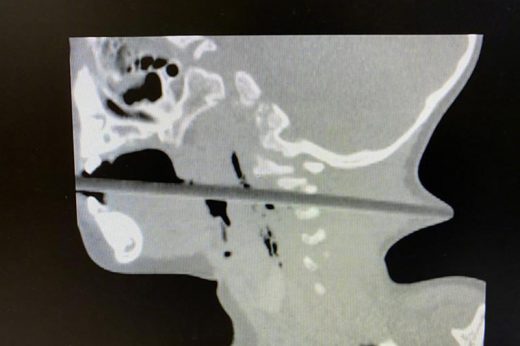

【家居意外】2歲童邊玩邊拿筷子插蘋果吃 不慎跌倒致筷子貫穿喉嚨